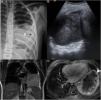

The initial diagnosis (Fig. 1) was confirmed in all cases by the pathological examination of a biopsy sample, supplementing the histological examination with immunohistochemistry and in situ fluorescence in the most recent cases (3/3 ALK +; 3/4 actin +; 2/3 vimentin +). All patients underwent complete resection of the tumour, with favourable outcomes in 4 out of the 5 observed in the followup (median duration, 7 years). One patient experienced malignant transformation of the tumour (inflammatory fibrosarcoma) and early relapse after surgery, requiring adjuvant therapy with ceritinib, which achieved a quick initial response, but ultimately with progression in a few months resulting in death.

(A) Radiograph of the ribcage showing infiltration and partial destruction of the posterior shaft of the left 8th rib (white arrow) associated with a large intrathoracic, extrapulmonary soft-tissue mass with faint amorphous calcifications (*) and mild pleural effusion. (B) Ultrasound image of the heterogeneous mass in the thorax. (C) T2-weighted magnetic resonance imaging (MRI), coronal plane and (D) intravenous contrast-enhanced, fat-saturated T1-weighted MRI, transversal plane, showing a lobulated mass in contact with the mediastinal, pericardial, axillary and diaphragmatic pleura with peripheral enhancement (arrow point) and necrosis in the central area.